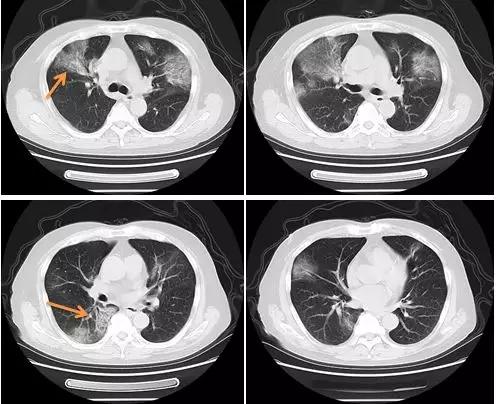

病例 1 男性,78 岁,发热 2 天

CT 示:两肺近胸膜下多发磨玻璃影;内见支气管充气征

病例 2 男性,30 岁,门诊就诊,主诉不详

右肺上叶尖段病变为实变影,余肺野内病变呈磨玻璃样改变

病例 3 女性,54 岁,发热

两肺野外周带多发点片状渗出、实变影,边界欠清,周围见晕征

病例 4 男性,34 岁,发热

右肺下叶后基底段单发磨玻璃样病变